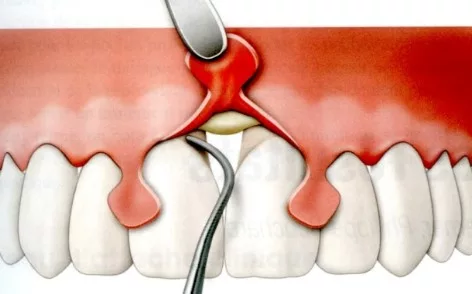

Des techniques chirurgicales de préservation papillaire permettent de régénérer les tissus parodontaux en garantissant leur maintien esthétique. Ces techniques chirurgicales avancées s’effectuent sous aides optiques grossissantes et avec des instruments micro chirurgicaux spécifiques.

• Réduire la présence de poches supérieures à 6 mm car le risque de progression de la maladie est élevé

• Éliminer le saignement, témoignage de la présence d’un tissu inflammatoire résiduel sous la gencive

• Reconstruire le tissu osseux perdu autours des racines afin de consolider